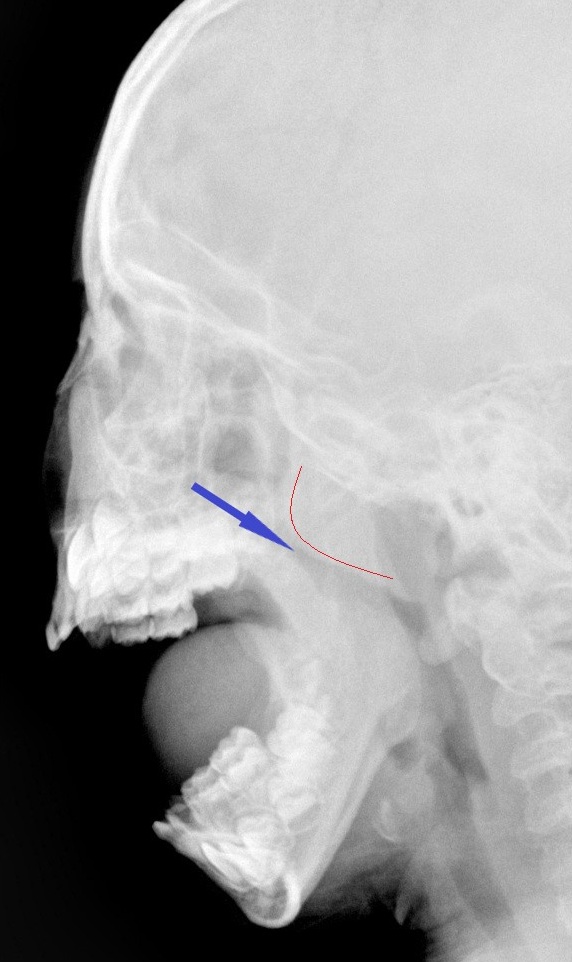

続いて アデノイド(鼻の一番奥にあるリンパ組織のかたまり)をファイバーとレントゲンでチェックしてみます。

ファイバーでアデノイドは大きく

レントゲンでも大きく(赤い出っ張り)、空気の通り道(青い矢印)は狭くなっていました。

病名はアデノイド肥大です。